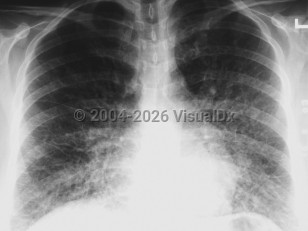

The incubation period for HCPS is 1-6 weeks but usually lasts for 2 weeks. Initial symptoms include the sudden onset of 3-5 days of fever, dry cough, fatigue, dizziness, myalgia, headaches, chills, nausea, vomiting, and abdominal complaints. The gastrointestinal symptoms can at times be severe and mimic surgical emergencies such as appendicitis, cholecystitis, or diverticulitis. Arthralgias and back pain occur less frequently. The disease progresses rapidly to fever, severe coughing, dyspnea, tachypnea, tachycardia, rales, diffuse pulmonary edema, acute respiratory distress syndrome (ARDS), and death. Rarely, some patients may develop disseminated intravascular coagulation (DIC). At the time most patients seek medical care, they usually require immediate intubation and mechanical ventilation.